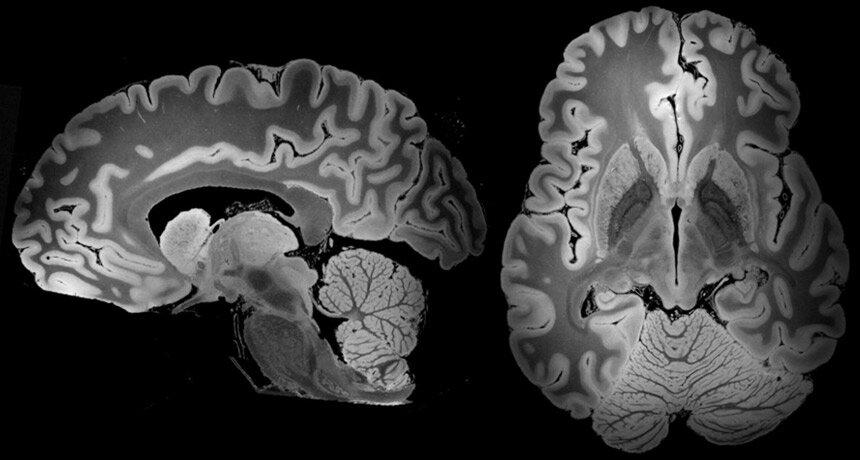

When a person’s head hits something or is shaken in an accident, the brain can suffer major damage. Even what may seem, at first, to be a minor bump can turn out to be much more.

The brain is at the core of every human being. It’s what makes up our thoughts, our movements, and our emotions. Everything we do, both voluntary and involuntary, relies on proper brain function, so an injury to your brain can be life-changing.

Traumatic brain injuries are caused by blows and jolts to the head, which jerk the injured person back and forth violently. The resulting damage varies, depending on the force of the impact and its cause.